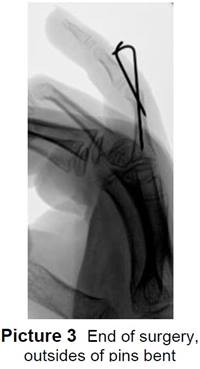

A doctor or health care provider will order an X-ray of the finger to show if there is a fracture (Picture 1).